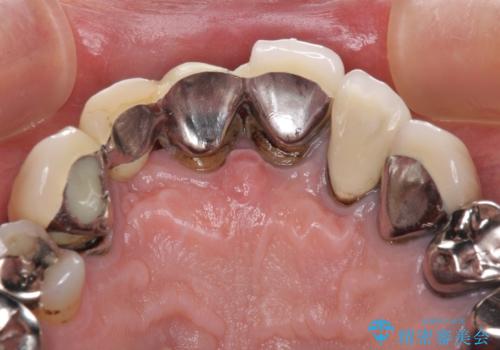

欠けてしまった前歯のブリッジをオールセラミックブリッジへ

- 前歯のブリッジのセラミックが欠けてしまい、作り直したいとのことで来院された患者様です。

犬歯はブリッジの中で虫歯が進行していたため、根管治療からやり直しをした後、オールセラミックブリッジにて補綴することとしました。